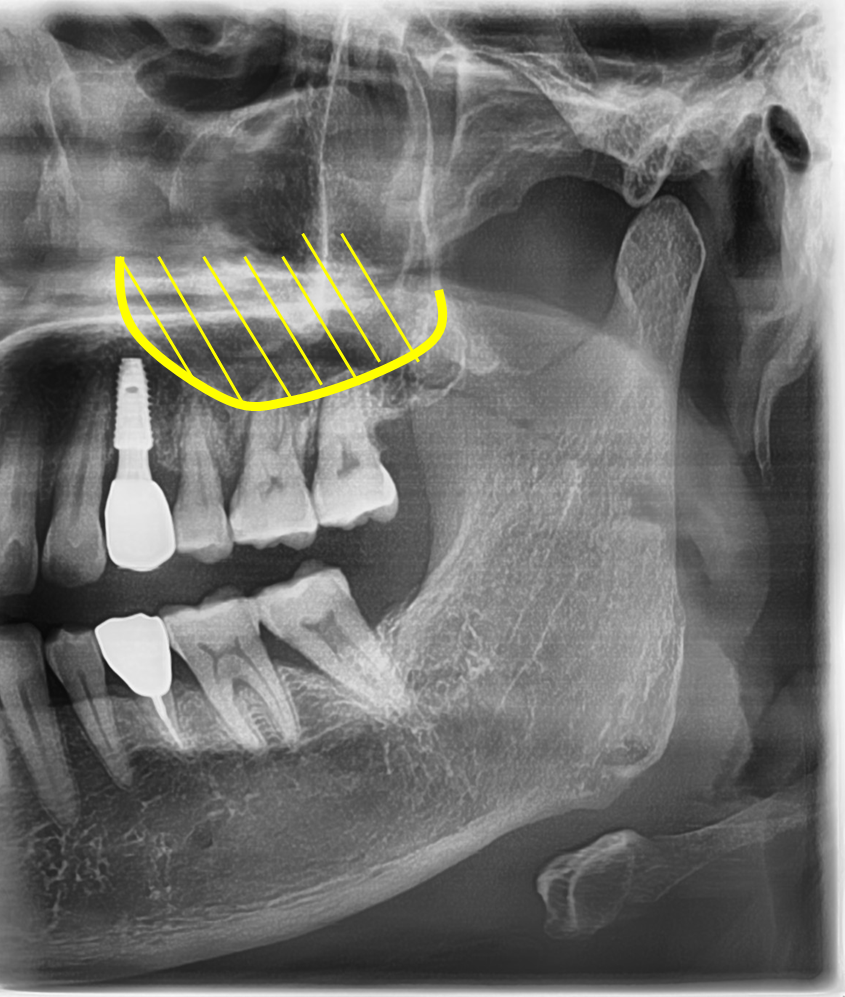

3. 뼈가 부족할 때 필요한 과정 – 상악동 거상술

이번 환자분의 경우, 상악 어금니 부위에 임플란트가 필요했습니다.

이 부위는 위쪽에 상악동이라는 빈 공간이 있어,

뼈가 부족할 때는 임플란트가 안정적으로 자리잡기 어렵습니다.

이럴 때 필요한 과정이 바로 상악동 거상술입니다.

상악동의 바닥을 살짝 들어 올리고 인공뼈를 보강하여

임플란트가 튼튼히 자리 잡을 수 있도록 돕는 방법입니다.

이번 치료에서도 비절개 방식과 함께 진행하여

잇몸 절개를 최소화하면서 뼈를 안정적으로 보강할 수 있었습니다.

그 결과 어금니 3개 모두 안정적으로 식립되었고,

과정을 쉽게 이해하실 수 있도록 준비한 참고 이미지입니다.